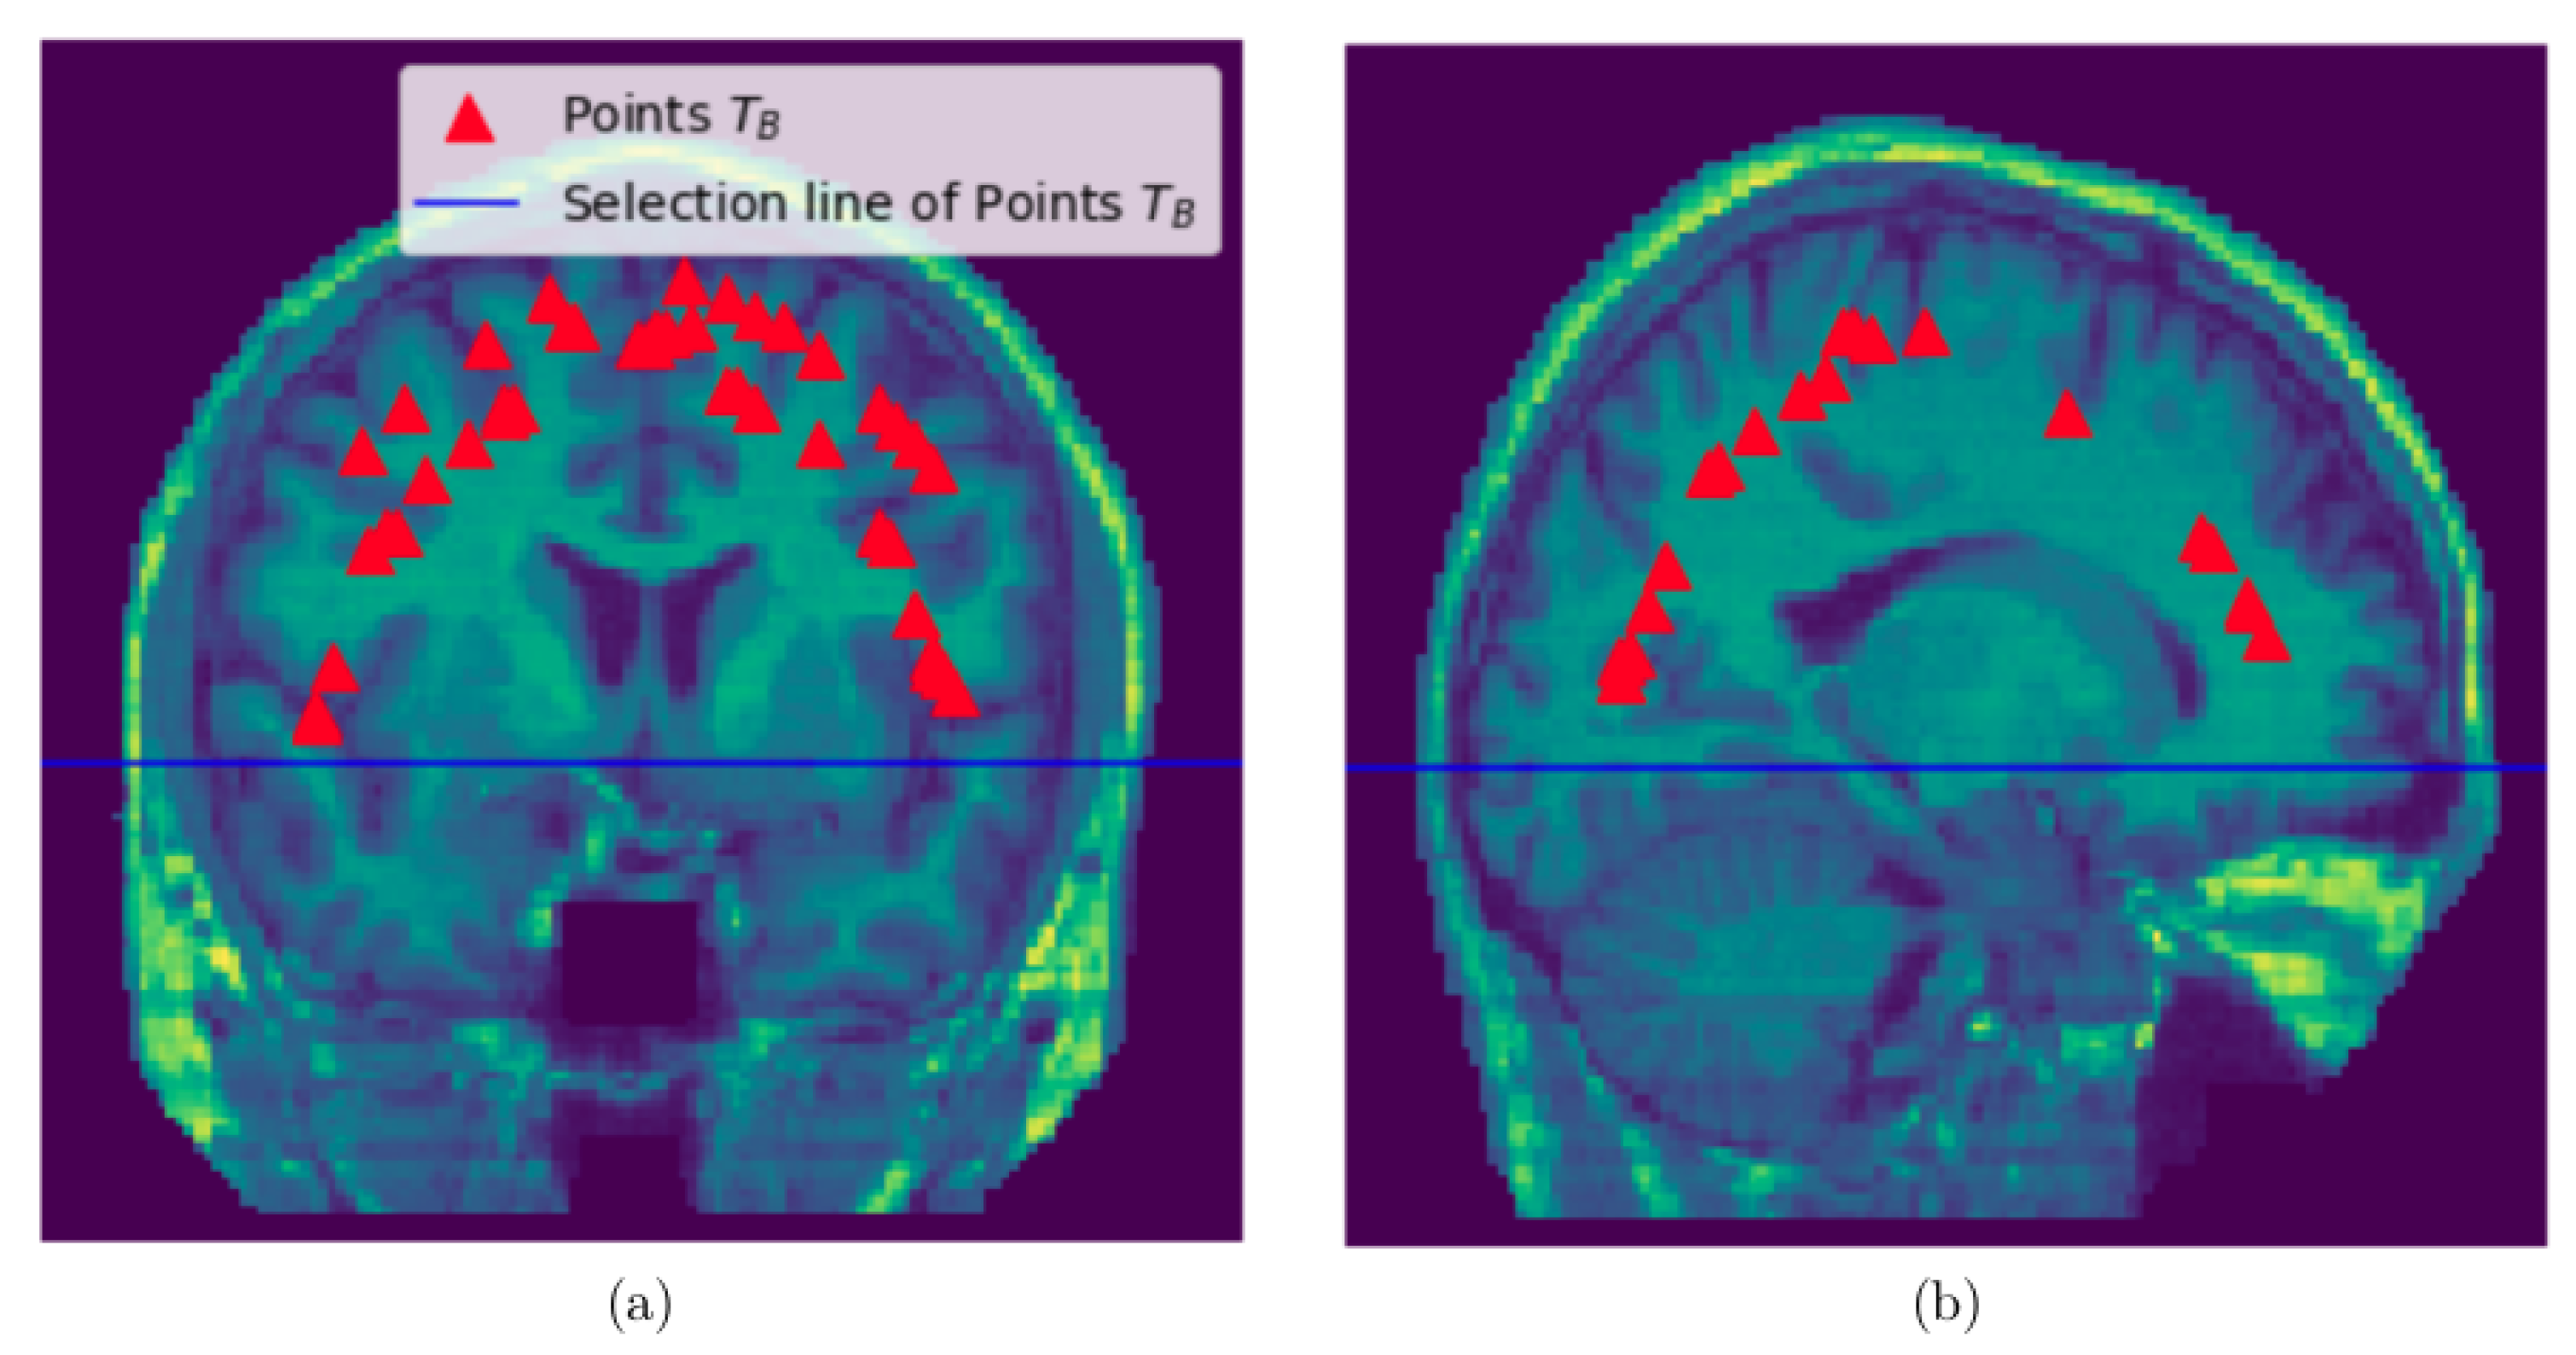

2.2.3. Sampling Points within the Brain, Non-Brain Tissues and Background